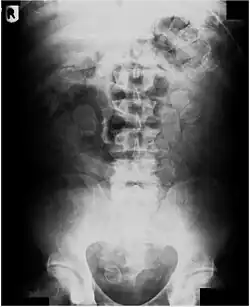

De detentiecel is voorzien van een speciaal toilet, waarmee ontlasting kan worden vastgehouden en onderzocht op drugscapsules. Men kan dit voorkomen door in te stemmen met een bodyscan: deze kan aantonen of er wel of geen bolletjes zijn.

Deze manier van smokkelen is zeer gevaarlijk. Het menselijk maag-darmkanaal zit vol agressieve chemicaliën die de bolletjes kunnen aantasten. Ook vet en olie kunnen het rubber aantasten. Hierdoor, of door te haastig dichtmaken, kunnen bolletjes makkelijk knappen. Hoe klein ze ook zijn, ze bevatten meer dan genoeg drugs om de koerier aan een overdosis te laten overlijden. Een ander risico is dat de bolletjes het spijsverteringskanaal kunnen blokkeren (ileus). Bij ontdekking wordt de koerier dan ook door de overheid gedwongen van de drugs ontdaan, tevens voor diens eigen veiligheid. Dit gebeurt door de bolletjes operatief te laten verwijderen in het ziekenhuis.